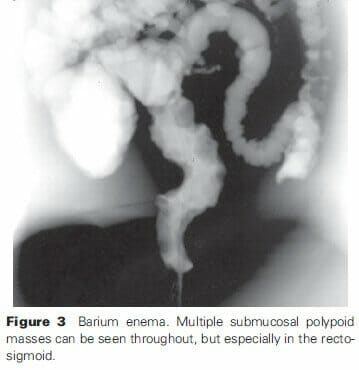

Contrast studies

The primary manifestation of hemangiomas and malformations that are identified with contrast studies occur in obstructing or polypoid lesions (Figure 3)33. Anterior displacement of the rectum and widening of the presacral space can infer the mass effect and soft-tissue component of large cavernous rectal malformations. These masses may collapse with air insufflation.